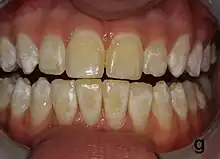

Dental fluorosis appears as a range of visual changes in enamel[4] causing degrees of intrinsic tooth discoloration, and, in some cases, physical damage to the teeth. The severity of the condition is dependent on the dose, duration, and age of the individual during the exposure.[1] The "very mild" (and most common) form of fluorosis, is characterized by small, opaque, "paper white" areas scattered irregularly over the tooth, covering less than 25% of the tooth surface. In the "mild" form of the disease, these mottled patches can involve up to half of the surface area of the teeth. When fluorosis is moderate, all of the surfaces of the teeth are mottled and teeth may be ground down and brown stains frequently "disfigure" the teeth. Severe fluorosis is characterized by brown discoloration and discrete or confluent pitting; brown stains are widespread and teeth often present a corroded-looking appearance.[1]

The adequate diagnosis of fluorosis can be diagnosed by visual clinical examination. This requires inspection of dry and clean tooth surfaces under a good lighting.[6] There are individual variations in clinical fluorosis manifestation which are highly dependent on the duration, timing, and dosage of fluoride exposure. There are different classifications to diagnose the severity based on the appearances. The clinical manifestation of mild dental fluorosis is mostly characterised a snow flaking appearance that lack a clear border, opaque, white spots, narrow white lines following the perikymata or patches as the opacities may coalesce with an intact, hard and smooth enamel surface on most of the teeth.[7] With increasing severity, the subsurface enamel, all along the tooth becomes more porous. Enamel may appear yellow/brown with discolouration and/or many pitted white-brown lesions similar to cavities. They are often described as "mottled teeth".[8] Fluorosis does not cause discolouration to the enamel directly, as upon eruption into the mouth, affected permanent teeth are not discoloured yet. In dental enamel, fluorosis causes subsurface porosity or hypomineralizations, which extend toward the dentinal-enamel junction as the condition progresses and the affected teeth become more susceptible to staining. Due to diffusion of exogenous ions (e.g., iron and copper), stains develop into the increasingly and abnormally porous enamel.[7]